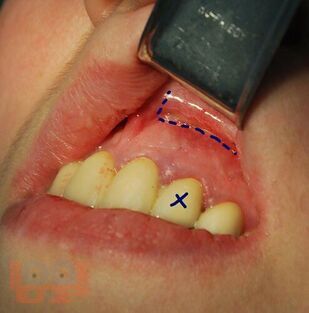

В учебном пособии на современном уровне освещены показания, противопоказания, техника выполнения зубосохраняющих операций при лечении хронических периодонтитов, а также методы предоперационной подготовки больных к хирургическому вмешательству и их послеоперационному ведению.